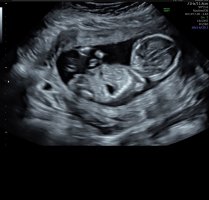

Ei näy nubia tässä kuvassaMiekin tulen kysymään osaako joku tästä meidän kuvasta jotain sanoa. Viikot 13+4. Mulla on sellainen tunne että poika tulisi, mutta tuosta nubista en osaa sanoa mitäänView attachment 138958